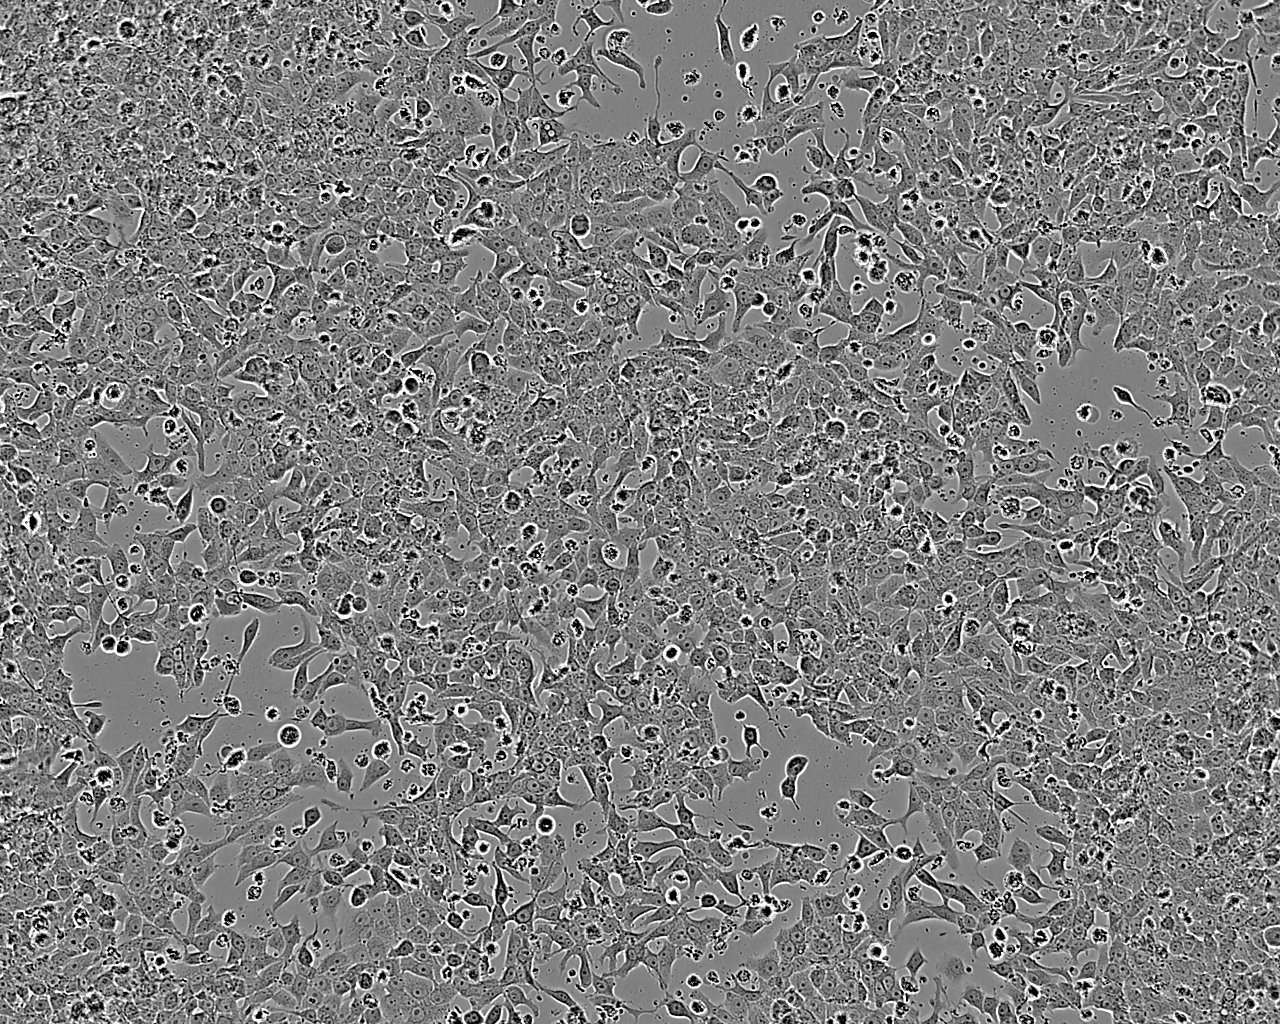

DMS 53人小細胞肺癌細胞(STR鑒定正確)

• 形態(tài)特征: 上皮細胞樣

• 生長特性: 貼壁

該細胞是從一位54歲未接受治療的白人小細胞肺癌患者的縱膈穿刺活檢組織中分離建系。細胞表達HLA I型和II型抗原。